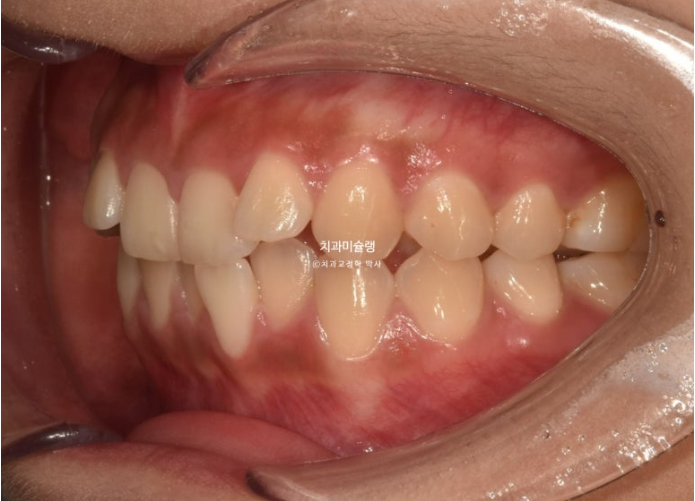

우측 교합관계는 1급에 가깝지만

좌측 교합관계는 2급입니다.

위 아래 치아들이 일대일로 물리면 2급 또는 3급 교합관계 입니다.

송곳니에서 큰어금니까지 절반씩 엇갈려 물리는 교합이 1급 교합입니다.

사랑니를 빼고 사랑니 공간으로 어금니를 후방이동 시켜 교합관계를 맞추고 덧니 해소할 공간을 얻기로 합니다.

돌출이나 뻗침은 없어서 비발치로 진행하는 것 입니다.